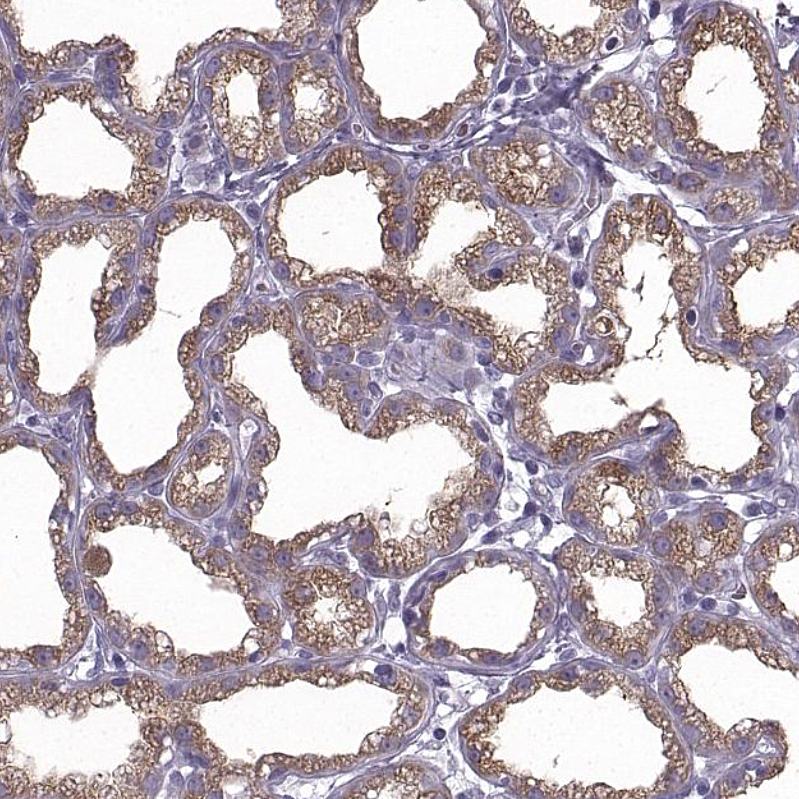

Immunohistochemistry analysis in human pancreas and liver tissues using HPA052701 antibody. Corresponding CEL RNA-seq data are presented for the same tissues.